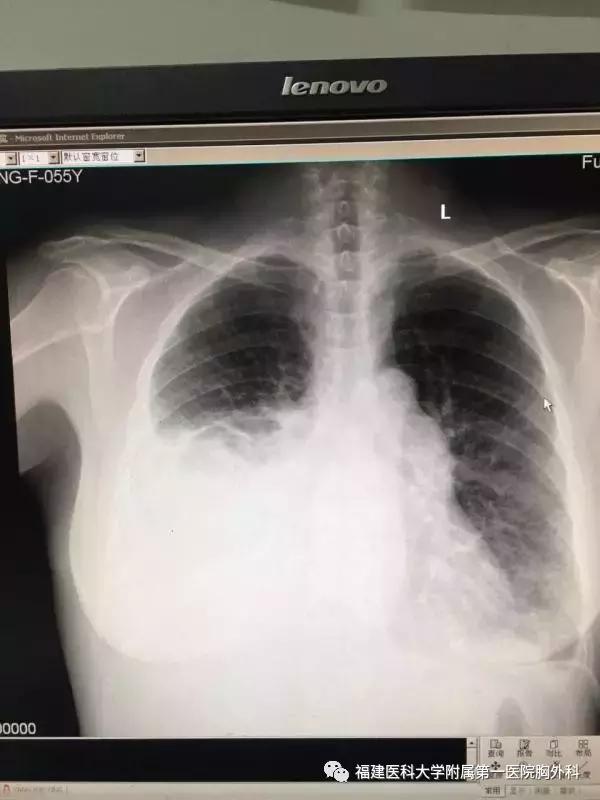

“当时我们接到时,患者胸腔积液严重,一侧引流量可达2000ml/天,不吸氧状态,血氧只有70左右,十分棘手。”

李旭主任率领整个团队对患者病情进行深入的分析,诊断为难治性乳糜胸,淋巴管肌瘤病可能,决定行“右侧胸导管结扎术”,但患者体质极为虚弱,双路面罩给氧,血氧才维持到85,做血气检查,氧分压只到正常人的一般,治疗难度大。暂时予以稳定病情后,选择手术,麻醉前氧分压仍旧只有40mmHg,麻醉师也是吓一大跳。

患者双侧胸腔积液并未大量减少,血氧依旧同前,但复查术后胸片,双侧肺已经复张的不错,可每天引流量仍是近1000ml。最后李旭主任采取逐个胸腔每日注射稀碘伏的办法,竟然引流量逐渐减少了,最后拔除胸腔引流管,患者不吸氧状态血氧还是维持80左右,但是没有气喘胸闷,顺利出院!